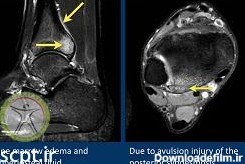

عکس ام ار ای پارگی رباط مچ پا

ام آر آی مچ پا یکی دیگر از اسکنهای شایع تصویربرداری پزشکی با ام آر آی است. در این اسکن به بررسی مچ پا ، پاشنه پا تاندون پا ، انگشتهای پا میپردازند.

پیچ خوردگی مچ پا و کشیدگی تاندون روی پا در آسیب های ورزشی جزو شایع ترین آسیب ها محسوب می شود. با توجه به اینکه این عارضه در اکثر ورزشکاران روی می دهد و می تواند عملکرد ورزشی را دچار اختلال نماید روش های درمانی موجود در کلینیک فیزیوتراپی مرکزی شریعتی برای درمان این گونه بیماران توصیه گردیده است.